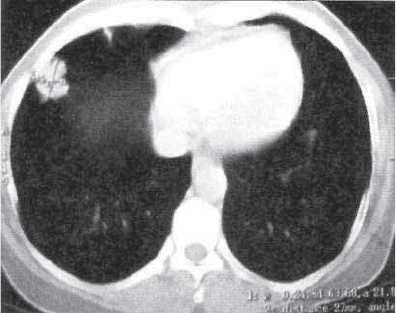

Рис. 13.18. Гамартохондрома правого легкого. КТ.

гамартохондромах возможны хрящевые включения, подобные

отложению солей кальция в туберкулемах (рис. 13.18). При

значительных размерах опухоли в прилежащей ткани отмеча-

ют деформацию легочного рисунка, фиброзные изменения.